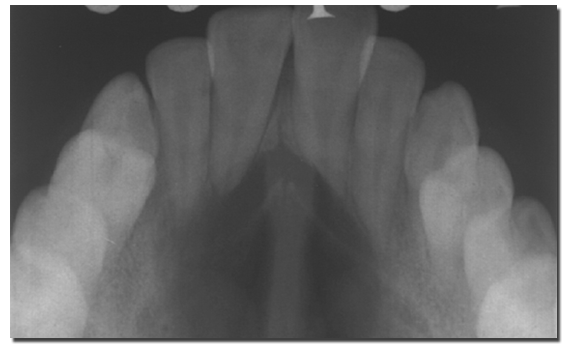

鼻腭管囊肿可发生于任何年龄,其中高发年龄为30~60岁。男性较多见。临床上常无明显症状,仅在X线检查或戴义齿时偶然被发现。最常见的表现为腭中线前部的肿胀,有时可伴疼痛或瘘管形成。X线照片上,常常难以区分鼻腭管囊肿和较大的切牙窝(incisive fossa)。X线片上的切牙窝宽度在6mm以下为正常范围,即使切牙窝前后径达10mm但无其他症状者,仍可能为正常,可定期复查而不必急于手术治疗。囊肿较大时,可见囊肿位于上颌骨中线,呈卵圆形放射透射区。